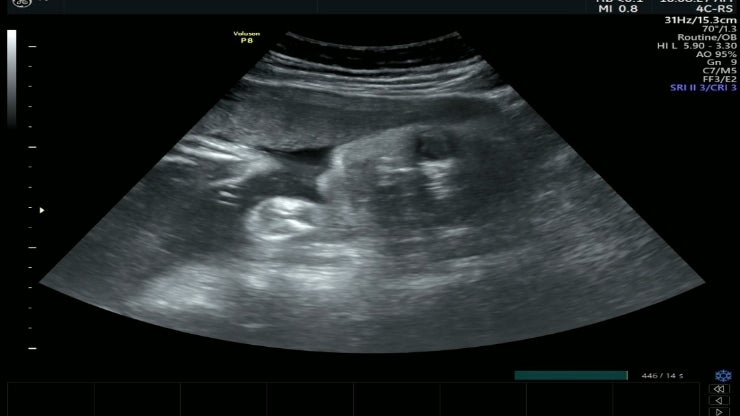

34w 0d 정기검진

34주입성 초음파보는데 눈뜨신 2.4키로 입도 오물거리고 눈도 깜빡이고 뭐가 그렇게 궁금했니 신기했다 볼...